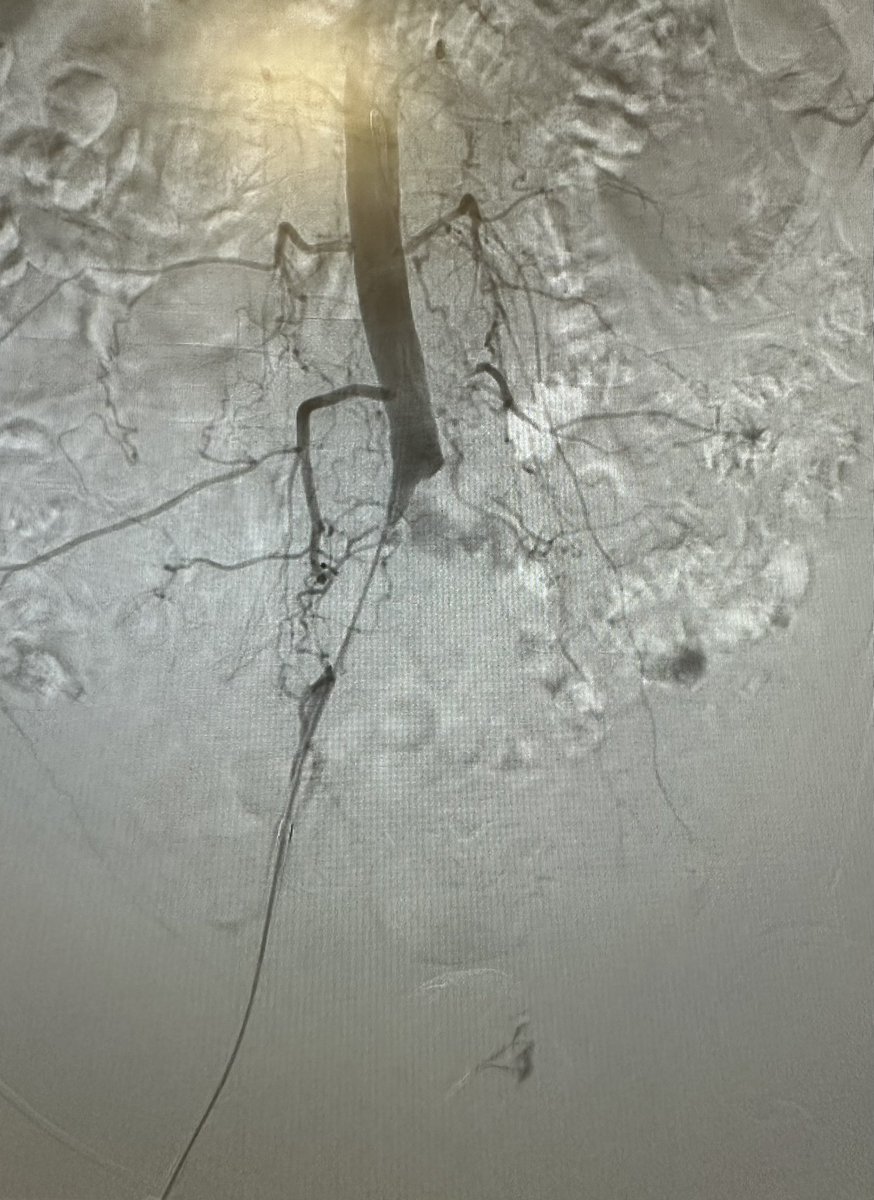

Interventional Radiologist @ NUH Singapore ex-BartsHealth Doctorate in Simulation-Based Medical Education #patientperspective #humanfactors #medicalplumbing